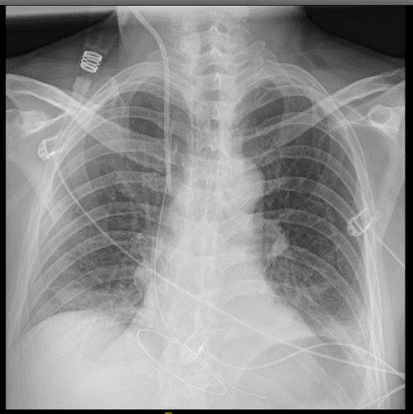

Hombre de 63 años sin antecedentes personales relevantes que consulta por dolor costal en relación con accidente de moto a baja velocidad (20 km/h). Exploración física: Valorado en el servicio de urgencias hospitalario con dolor a punta de dedo en parrilla costal izquierda a nivel de 8º-9º arcos costales anteriores izquierdos, sin deformidad ni volet costal. Hemodinámicamente estable a su llegada con saturación basal de O2 al 98%. Auscultación cardiopulmonar normal y abdomen sin defensa ni signos de irritación peritoneal. Pruebas complementarias: Dado el mecanismo lesional se solicita radiografía de tórax donde se objetivan fracturas costales no desplazadas de 8º-9º-10º arcos costales izquierdos. Se solicita análisis de sangre y se deja en observación para control del dolor.